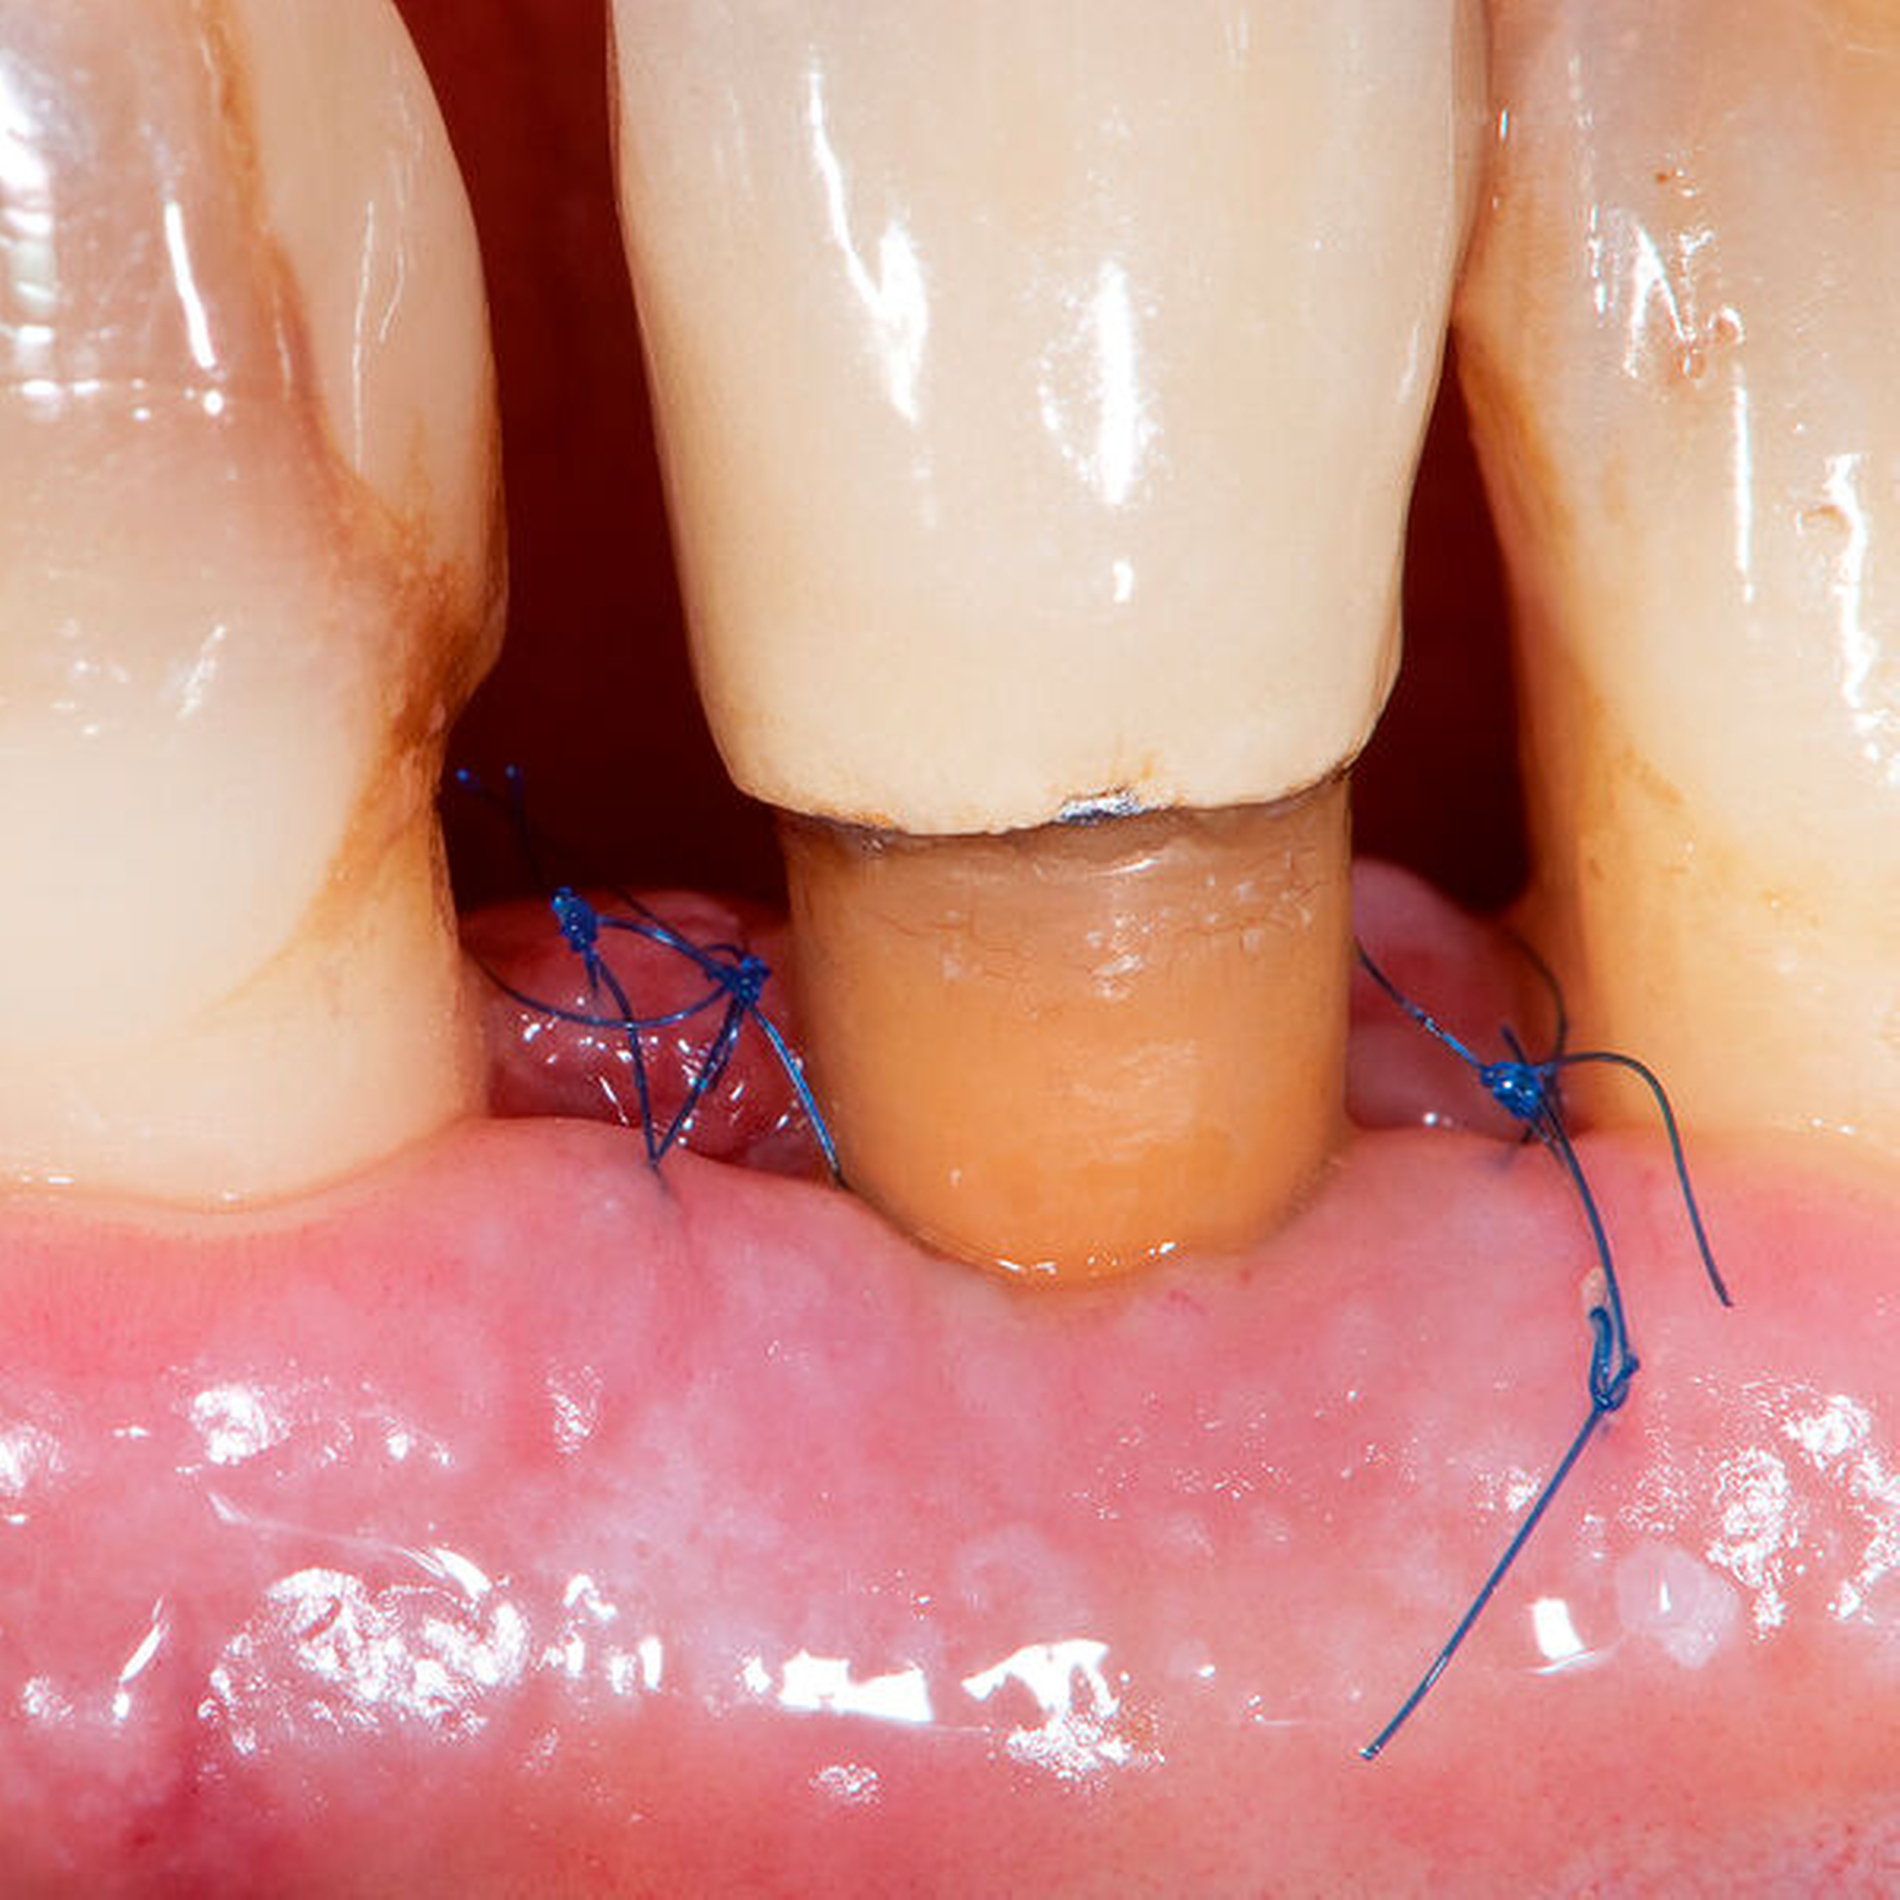

Während der Anfänge mikrochirurgischen Arbeitens in der Oralchirurgie zu Beginn der 1990er-Jahre wurden kurzerhand Instrumente und Nahtmaterialien aus anderen Fachdisziplinen, die die Mikrochirurgie bereits implementiert hatten, in die mikrochirurgische Parodontalchirurgie übernommen. Allein schon die Größe dieser Instrumente und Nadel-Faden-Kombinationen machte die Verwendung eines dentalen Operationsmikroskops während dieser Zeit obligat. Da sich jedoch die ergonomischen Anforderungen beispielsweise in der Gefäß- und Handchirurgie ganz wesentlich von denen oralchirurgischer Eingriffe unterscheiden, wurden nach und nach mikrochirurgische Instrumente und Nahtmaterialien speziell für den Einsatz in der oralen Mikrochirurgie entwickelt. Die doch sehr indi-viduellen und speziellen Anforderungen führten unter ergonomischen Gesichtspunkten zu vergleichsweise größeren und schwereren Instrumenten sowie dickeren und längeren Nadeln in Kombination mit dünnen Fäden der Größen 7.0, 8.0 und 9.0, wie sie bis heute in keiner anderen mikrochirurgischen Disziplin zur Anwendung kommen (Abbildungen 3 und 4). Als vorteilhaft erweist es sich vor diesem Hintergrund, dass die Dimensionen dieser gegenwärtig verwendeten Instrumente und Nahtmaterialien – Stand heute – problemlos mit Lupensystemen und Vergrößerungsfaktoren von 4.5x bis 6.0x eingesetzt werden können. Damit findet sich die orale Mikrochirurgie zum gegenwärtigen Zeitpunkt irgendwo zwischen konventioneller Makrochirurgie und traditioneller Mikrochirurgie mit dem großen Vorteil wieder, dass die Anwendung von Operationsmikroskopen mit den zuvor genannten Schwierigkeiten und Nachteilen nicht zwingend erforderlich ist.

Neue Trends und Entwicklungen in der modernen Oralchirurgie gehen allerdings in Richtung sehr feiner Skalpellklingen, die extrem kleine chirurgische Zugänge ermöglichen und noch weniger invasive mikrochirurgische Techniken erlauben [Rebele et al., 2014; Zuhr et al., 2018]. Auf dieser Grundlage lässt sich vermuten, dass die mikrochirurgischen Instrumente und Nahtmaterialien in der oralen Mikrochirurgie in Zukunft wieder kleiner werden könnten und deshalb auch wieder höhere Vergrößerungsfaktoren für die zu ihrer Anwendung erforderlichen Sehhilfen notwendig werden (Abbildungen 5 bis 16). So wie es in anderen mikrochirurgischen Fachdisziplinen bereits heute Realität ist, könnten vor diesem Hintergrund auch zukünftige Generationen dentaler Operationsmikroskope im Hinblick auf Flexibilität, Workflow und Anwenderfreundlichkeit verbessert und auf diese Weise wieder einen festen Platz in einer oralchirurgisch tätigen Praxis einnehmen. Eine gute Perspektive könnten auch innovative Lupensysteme darstellen, die bereits heute mit Vergrößerungsfaktoren von 9.0x bis 10.0x angefertigt werden können.